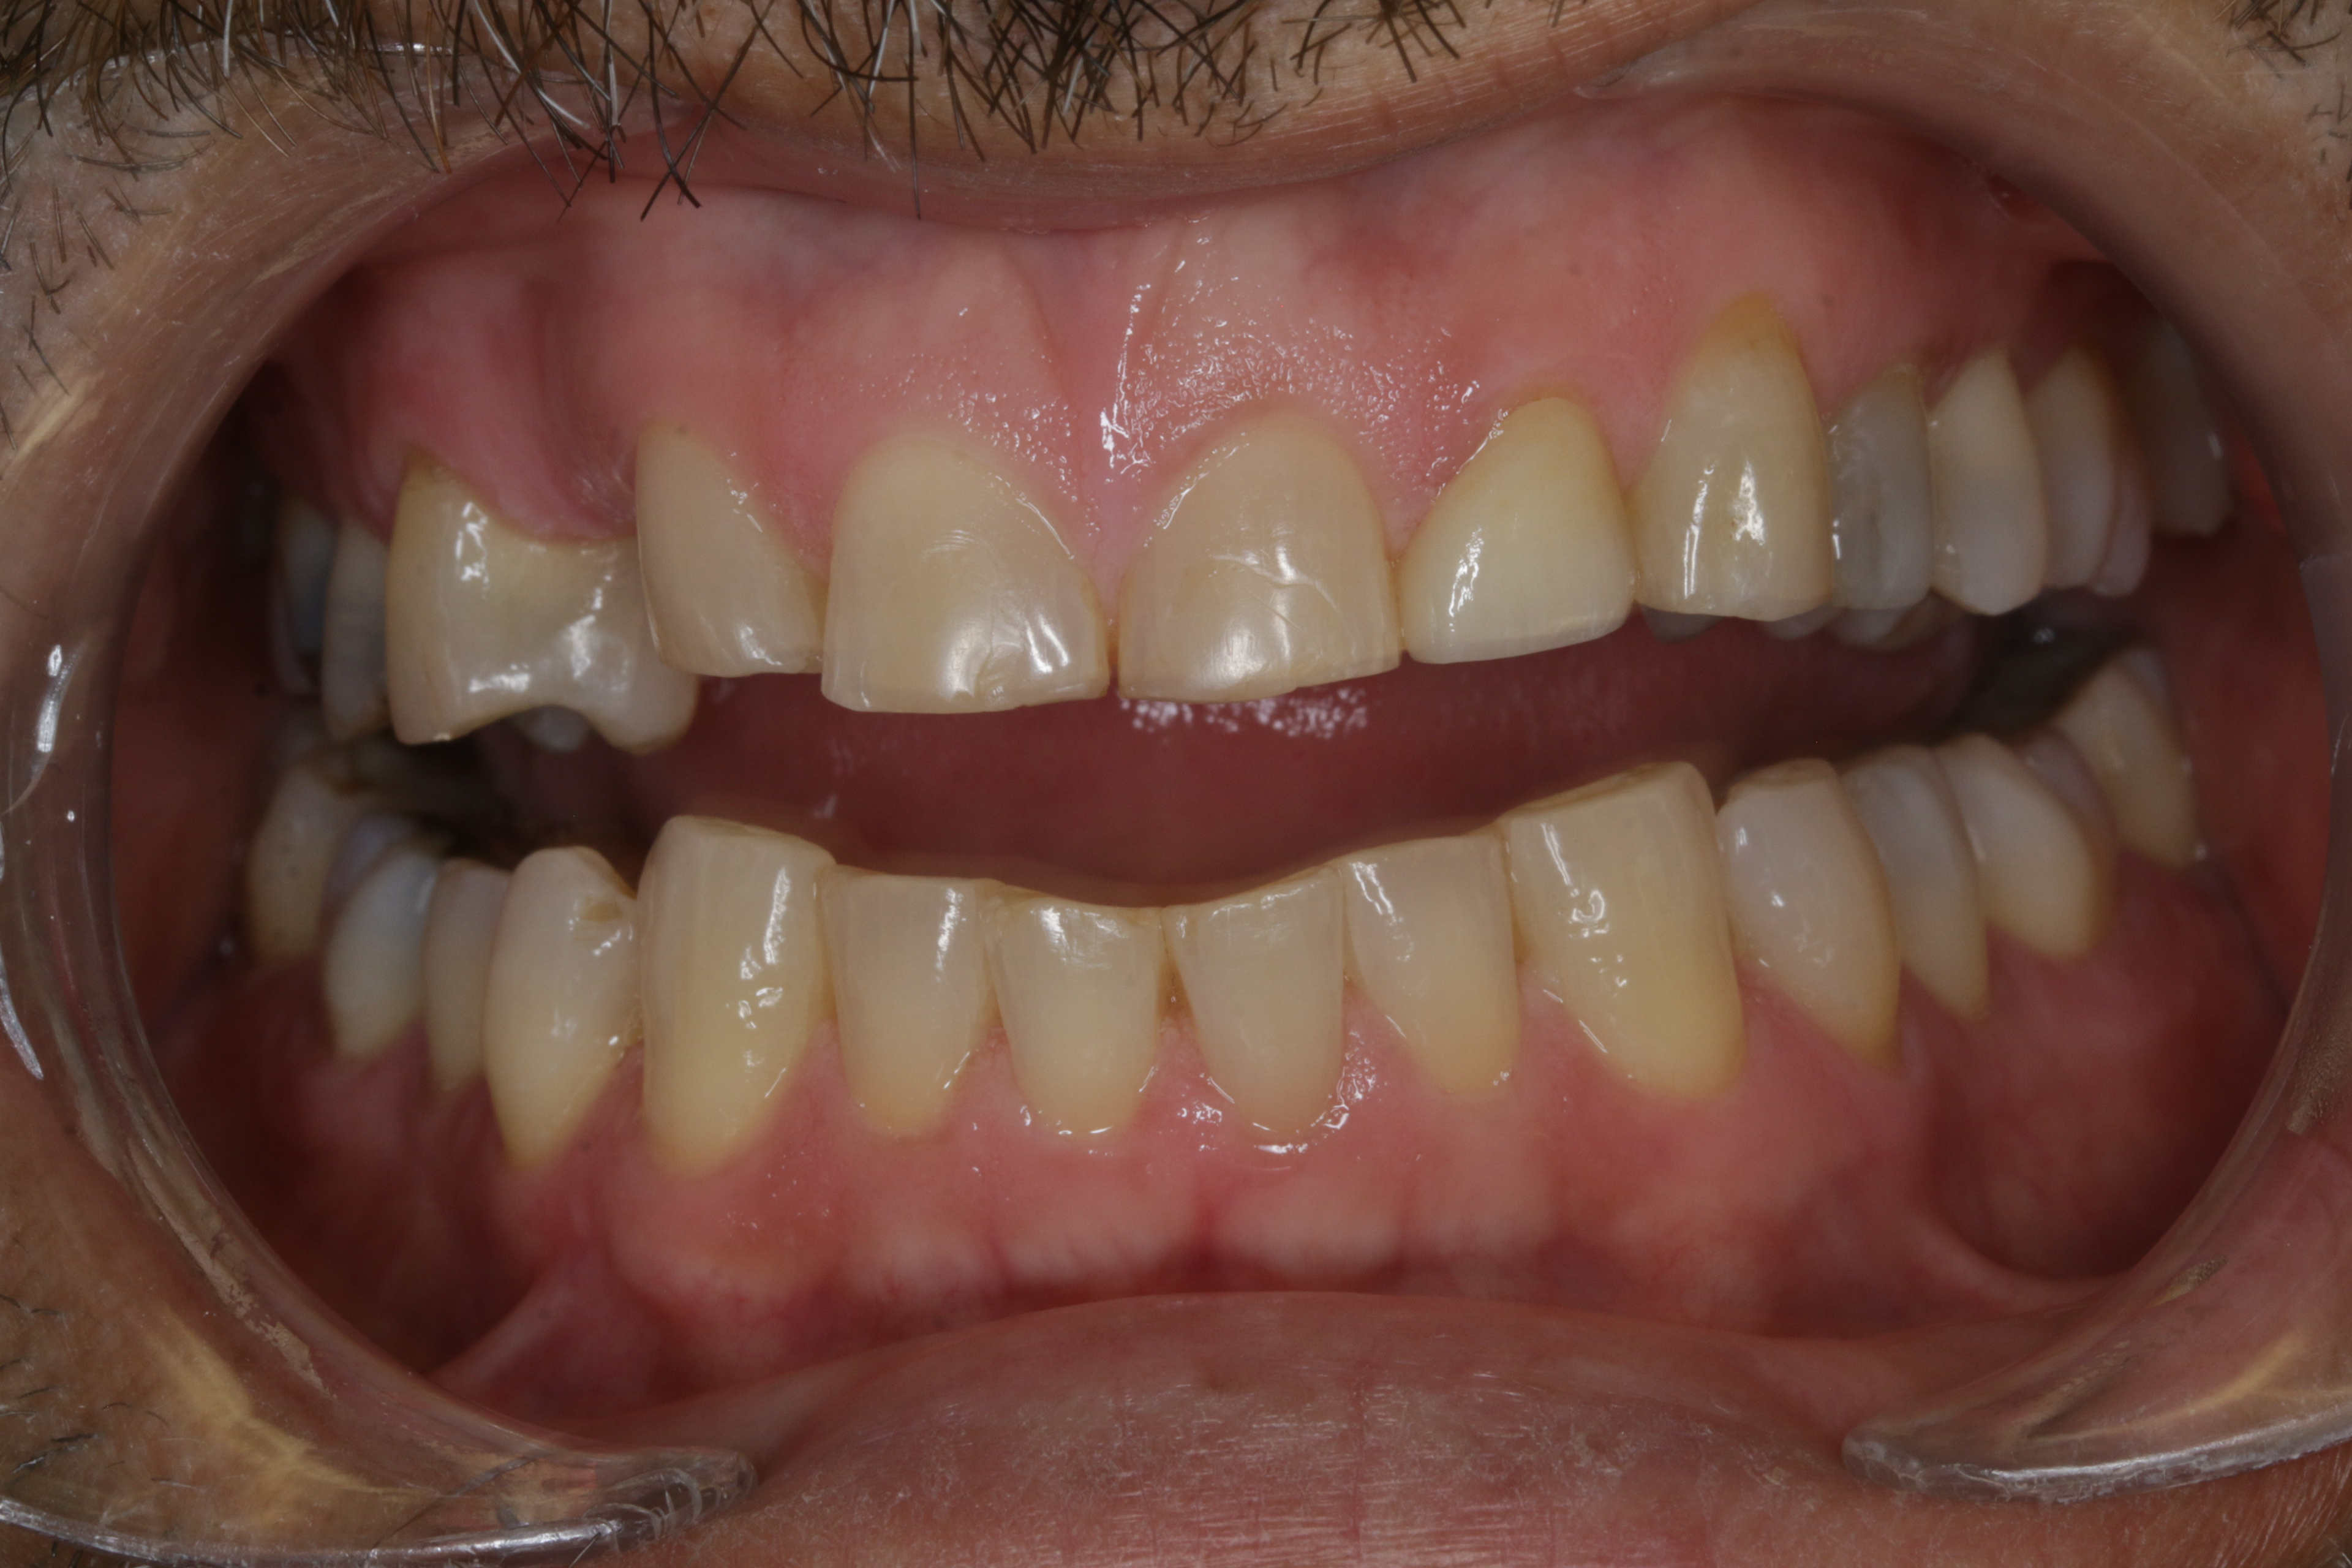

INITIAL RECORDS

BEFORE